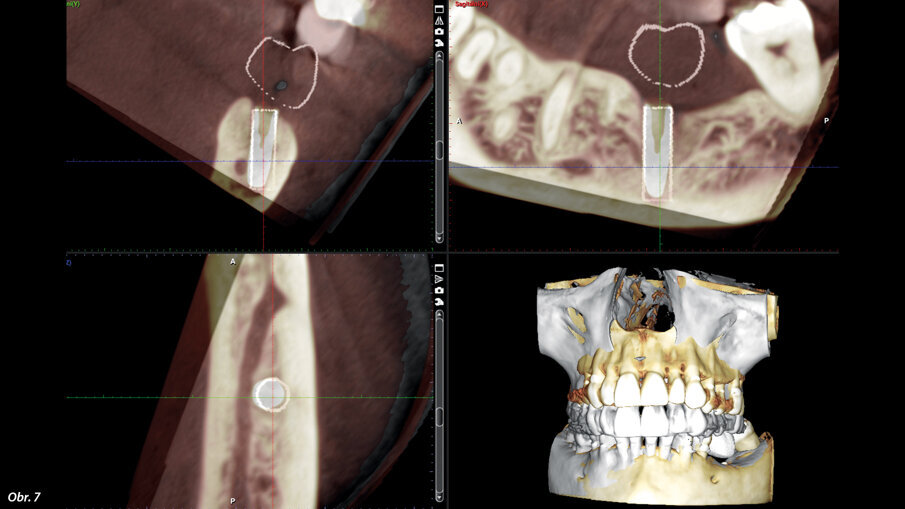

Přesnost navigované implantace – plánovaná pozice je znázorněna bílým válcem. Implantát byl zaveden dle plánu s klinicky nevýznamnou odchylkou.

Po zavedení bylo provedeno kontrolní CBCT, které bylo graficky porovnáno s plánovacím CBCT. Plánovaná pozice je vyznačena bílým válcem (obr. 7). Implantát byl zaveden dle plánu s klinicky nevýznamnou odchylkou. Čas, který jsme věnovali plánování, v kombinaci s kvalitním instrumentáriem a správně vytištěnou šablonou umožnily rychlý zákrok s predikovatelným výsledkem.